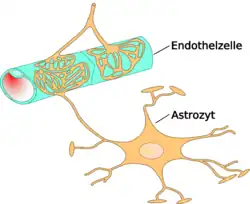

Diese besondere Abgrenzung des Bluts (intravasal) vom extravasalen Raum in Gehirn und Rückenmark ist bei allen Landwirbeltieren (Tetrapoda) ausgebildet und ermöglicht es, für das Nervengewebe eigene Milieubedingungen aufrechtzuerhalten (Homöostase). Im Wesentlichen wird diese Barriere von Endothelzellen gebildet, die hier in den kapillaren Blutgefäßen über Tight Junctions eng miteinander verknüpft sind.

Das wesentliche Element der Blut-Hirn-Schranke bilden die Endothelzellen mit ihren Tight Junctions. Für Funktion sowie Aufbau und Entwicklung der Blut-Hirn-Schranke sind jedoch noch zwei andere Zelltypen, die Perizyten und die Astrozyten, von großer Bedeutung.[1] Die Zell-Zell-Interaktionen zwischen Endothelzellen, Perizyten und Astrozyten sind so eng wie bei sonst keinen anderen Zellen. Diese drei Zelltypen zusammen bilden die Blut-Hirn-Schranke der meisten Wirbeltiere, die endotheliale Blut-Hirn-Schranke.[5][6] Die nachfolgenden anatomischen Angaben beziehen sich auf die endotheliale Blut-Hirn-Schranke der Wirbeltiere. Die bei einigen Wirbeltieren und vielen Wirbellosen ausgebildete gliale Blut-Hirn-Schranke wird am Ende dieses Kapitels gesondert aufgeführt.

Astrozyten sind sternförmig verzweigte, im Vergleich zu den Perizyten deutlich größere Zellen aus der Familie der Makroglia. Sie werden dem Zentralen Nervensystem zugerechnet und sind nach der Geburt noch teilungsfähig. Bei höheren Wirbeltieren haben sie keine direkte Schrankenfunktion, auch wenn sie die Kapillargefäße im Gehirn zu etwa 99 % mit ihren Endfüßchen bedecken.[6][53] Sie stehen allerdings in unmittelbarer Wechselwirkung mit den Endothelien.[54] Astrozyten induzieren in den Endothelien der zerebralen Blutgefäße die Funktion der Blut-Hirn-Schranke. Dies wurde durch Transplantationsversuche nachgewiesen. Zerebrale Blutgefäße, die in periphere Organe verpflanzt wurden, verhielten sich wie die dort vorhandenen „normalen“ Kapillaren und bildeten beispielsweise Fenestrierungen aus. Im umgekehrten Versuch nahmen periphere Kapillaren, die in das Zentralnervensystem verpflanzt wurden, den dortigen Phänotyp mit Tight Junctions an.[1][55] Auch in In-vitro-Versuchen zeigt sich der Einfluss der Astrozyten auf die Phänotypausprägung der Endothelien. In Co-Kulturen aus Astrozyten und Endothelzellen weisen die Endothelien eine höhere Dichtigkeit auf als in reinen Endothelkulturen.[56]

Astrozyten schütten eine Reihe von Botenstoffen aus, die die Durchlässigkeit des Endothels im Sekunden- bis Minutenbereich modulieren können.[57] Umgekehrt schütten die Endothelzellen den Leukämieinhibierenden Faktor (LIF), ein Zytokin der Interleukin-6-Klasse, aus, der die Differenzierung der Astrozyten induziert.[57] Der Abstand der Astrozytenfüßchen zu den Endothelzellen und den Perizyten beträgt nur 20 nm.[6][58]